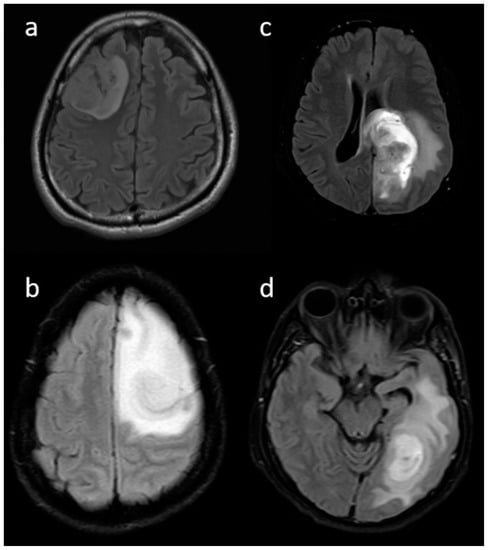

3.2. MRI Parameters of IDH-Wildtype vs. Mutant Phenotype Tumors